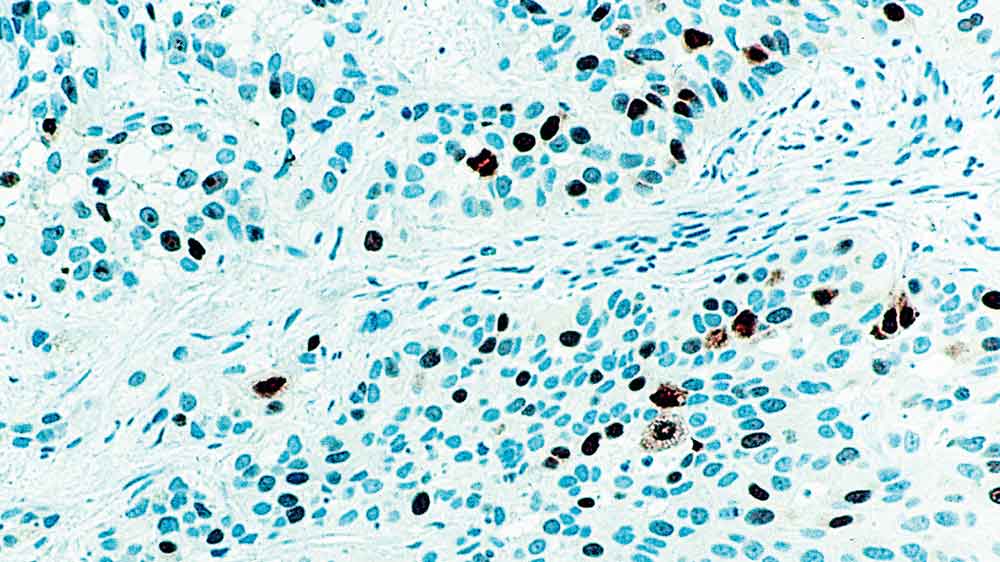

Human bladder tumor: immunohistochemical staining for Topoisomerase II alpha. Note intense nuclear staining of malignant cells and occasional mitotic figures. Topoisomerase II Alpha: clone 3F6

Topoisomerase II alpha is an essential nuclear enzyme involved in DNA replication and is a target for many anti-cancer drugs used for cancer therapy. Decreased expression of topoisomerase II alpha is the predominant mechanism of resistance to several chemotherapeutic agents. A significant variation in the range of expression of this protein has been reported in many different tumors. Reports of the analysis of primary breast tumors have indicated that topoisomerase II beta is more widely expressed than topoisomerase II alpha. Topoisomerase II alpha expression and activity is linked to the cell cycle and is associated with the proliferation status of cells.